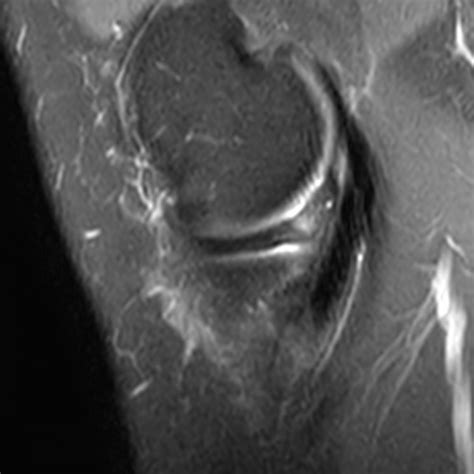

• Magnetic Resonance Imaging (MRI) to provide detailed images of the meniscus and surrounding structures. MRI is particularly useful in identifying the location and extent of the tear.

Surgical treatment for a Bucket Handle Tear Meniscus typically involves arthroscopic surgery. This minimally invasive procedure allows the surgeon to repair or remove the torn portion of the meniscus using small incisions and specialized instruments. The specific surgical approach depends on the location and extent of the tear: